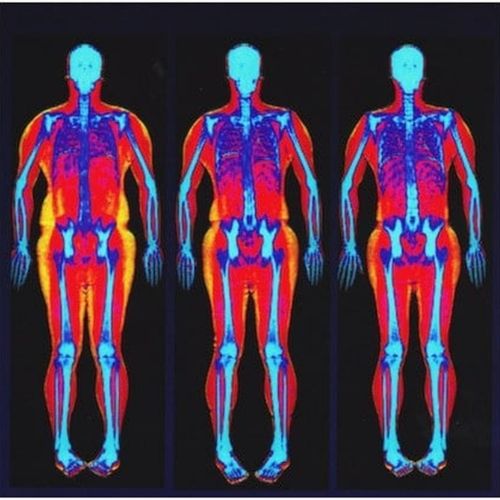

Bone strength and density evaluation

Musculoskeletal and abdominal imaging.